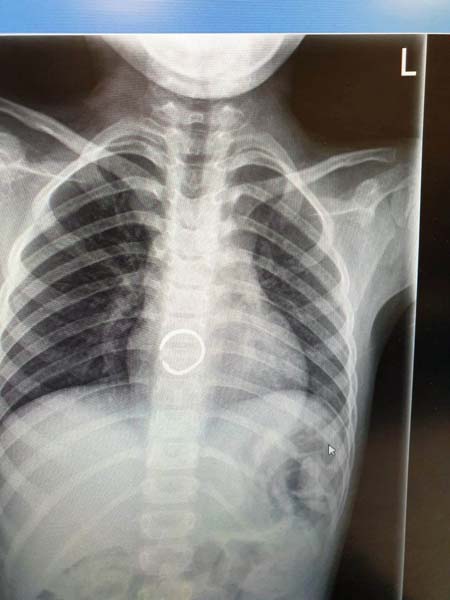

نجح الطاقم الطبي في مستشفى زيف في صفد ، في استخراج خاتم من داخل مريء طفلة ( 6 سنوات ) ، وذلك بعد اجراء عملية لها واخضاعها للتخدير الكلي .

وافاد مستشفى زيف في صفد ان" العملية التي اجريت للطفلة سمحا سويسا من صفد تعتبر بمثابة انقاذ لحياتها وذلك بعد ان ابتلعت الخاتم المرصع بالمجوهرات وشعرت باوجاع في منطقة الصدر، فتم نقلها الى مستشفى زيف في صفد وبعملية حذرة جدا من اجل عدم جرح ألأعضاء الداخلية للطفلة ، تم استخراج الخاتم بنجاح وتسريح الطفلة في اليوم التالي وهي بصحة جيدة " .